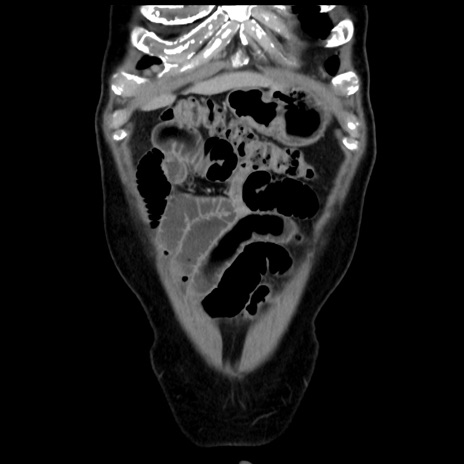

症例16(冠状断像)

【症例】 70歳代男性

【主訴】 腹痛、嘔吐

【現病歴】 約1ヶ月前より間欠的に腹痛と嘔吐あり、当院消化器内科を受診したところCTで多発する肝臓のLDAを指摘され、精査中であった。以降は消化器症状は安定していたが、2日前より嘔気と腹痛があり、同日より排便・排ガスが消失した。改善認めず、 本日、救急外来を受診した。